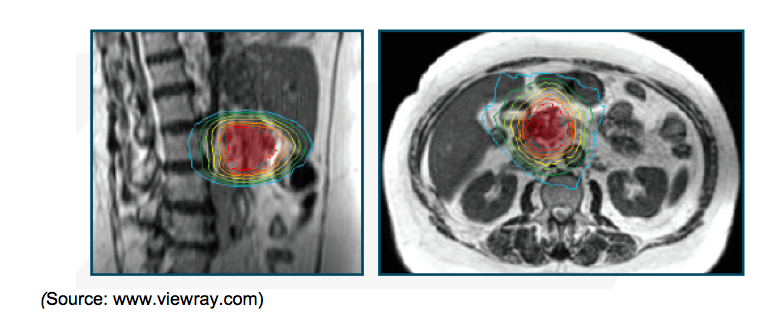

Each radiation source is equipped with a double-focused Multi-Leaf Collimator (MLC), with 1.05cm leaf width and a maximum field size of 27.3cm x 27.3cm at the isocenter distance of 105cm, resulting in minimal beam penumbra for precision. It is well accepted that X-ray radiation techniques can control many cancers if the radiation beam can be adequately controlled to target the cancerous tissue. MRIdian’s MLCs help in defining the irradiation beam precisely to target cancerous cells. A pneumatic drive moves the sources in and out of the depleted Uranium shield. The system design enables axial radiation beam access to the patient with minimal attenuation. During treatment, tissue/organ structures are observable in continuous and simultaneous fast planar images; in one sagittal plane at four frames per second or in three parallel sagittal planes at two frames per second. The gantry containing the sources is positioned between two superconducting magnets. Patient bore diameter is 70cm and accommodates large patients. Imaging takes place in a 50cm diameter spherical volume.

Software: The MRIdian software possesses the capability to track the soft-tissue continuously in MRI images. Using this software, the on-table ART process can be implemented in less than two minutes, and includes: auto-contouring, dose prediction and treatment plan optimization. For contouring, the software will automatically delineate the tumor border. This process allows the clinician to make refinements to the region of interest before delivering treatment, if necessary. Dose prediction can be calculated immediately following auto-contouring. The software then generates a treatment plan in about one minute, allowing time to re-plan while the patient is on the table. While the radiation dose is being delivered, the software analyzes the acquired images to determine the tumor’s or organ’s location relative to set boundaries. If the targeted tumor or a critical organ moves outside the defined boundary, which can occur due to physiological motions such as respiration, cough or digestion, the treatment beams will automatically pause and will automatically resume when the tumor moves back into the target zone. Physicians can set both spatial and time thresholds for pausing treatment delivery. This enables the system to account for tumor and patient motion during treatment.

Clinical Studies: Instead of relying on existing bones or implanted fiducial markers, the MRIdian system’s real-time imaging enables the physician to track the movement of the tumor and the surrounding healthy tissue directly. With better soft tissue imaging provide by MRI, the patient can be aligned more accurately for treatment. When the tissues have changed and the treatment plan is no longer acceptable, on-table ART allows for the reshaping of the dose to maximize target coverage and healthy tissue sparing without moving the patient. During beam delivery, the treatment beam automatically pauses in situations where a tumor is in close proximity to a critical organ, such as the heart during lung and breast cancer treatments or the rectum during prostate cancer treatments. The real-time tracking of tissues has enabled physicians to treat patients who would not have been considered for radiation therapy.

Pancreas: Most pancreatic cancers are difficult to resect due to the organ’s proximal location to the celiac and superior mesenteric arteries along with the portal vein in the abdominal cavity. The head of the pancreas is located within the curve of the duodenum. It is important to track the portal vein or pancreatic head during treatment because the duodenum is very sensitive to radiation. MRIdian allows you to continuously monitor the target area with a gated breathing technique.